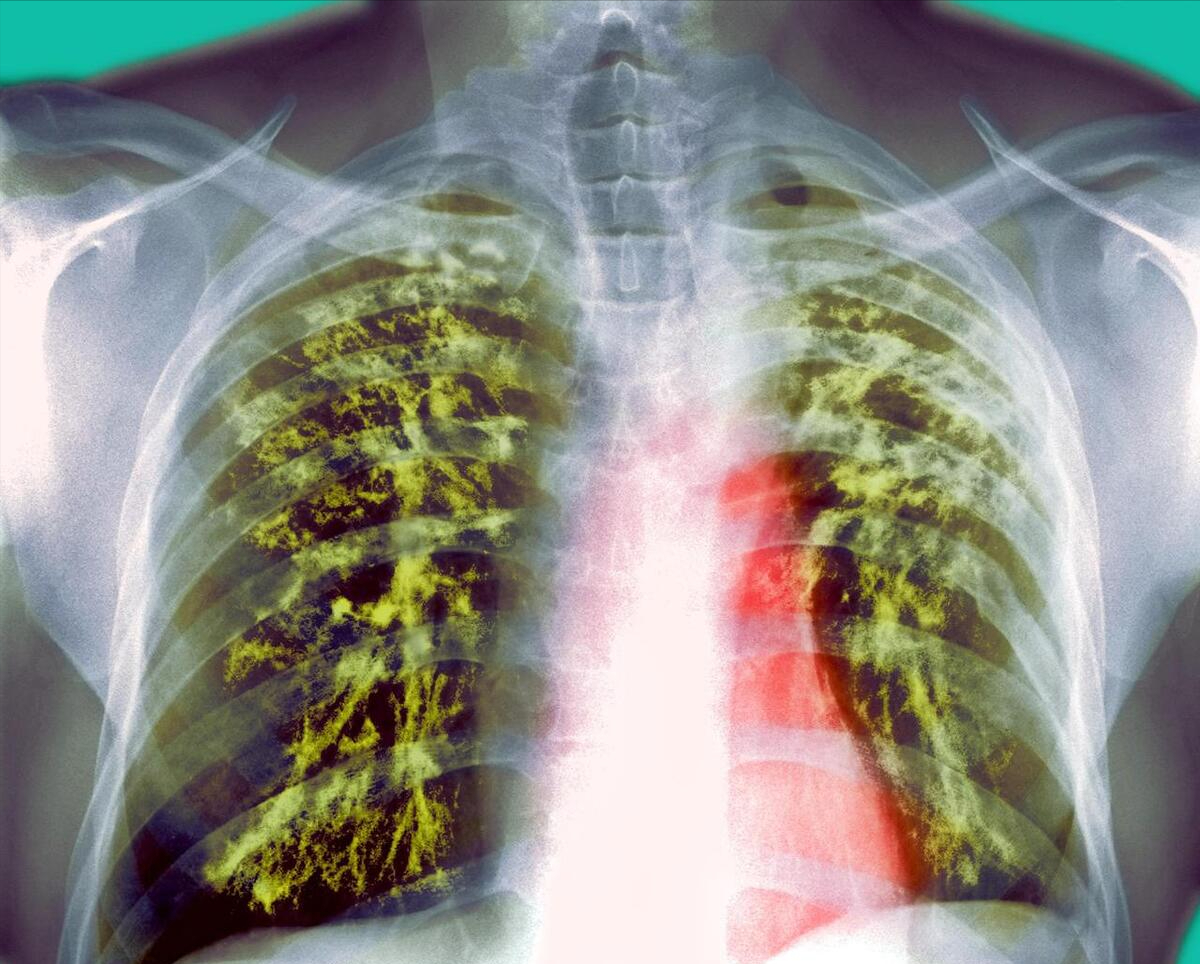

矽肺是由于长期吸入大量含有游离二氧化硅的粉尘所引起的肺部疾病,其